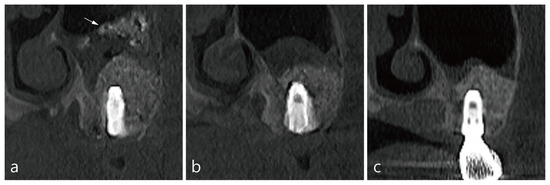

3. Case 1

4. Case 2